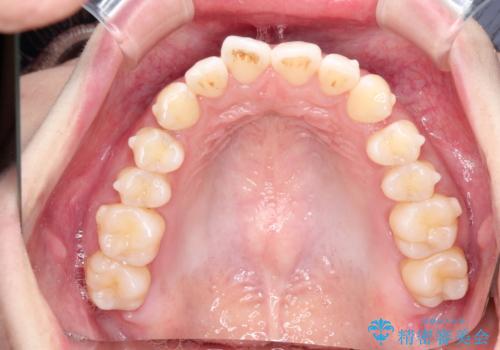

初診時の歯並びの状態としては、上下にガタガタがある状態であり、特に上の前歯(左上1番)の捻じれを最も気にしていらっしゃいました。

前歯の捻じれを改善するためにスペースを作る必要があり、前歯の歯の間を削って簡単に直す方法もありますが、奥歯のズレが認められたため、大臼歯後方のスペースを利用し、根本的な原因からしっかりと治療を行いました。